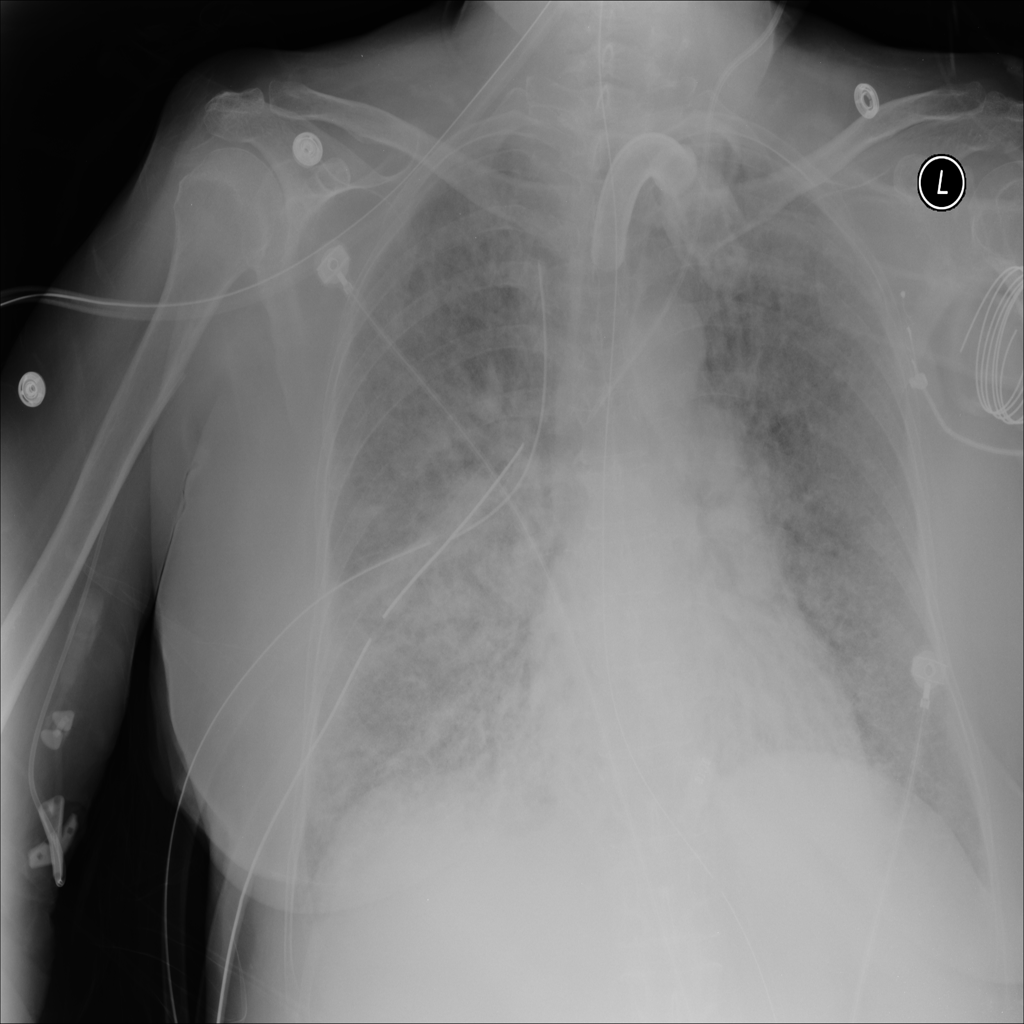

PAT-C1A7 · IMG-004Consolidation

PAT-C1A7 · IMG-004

PA